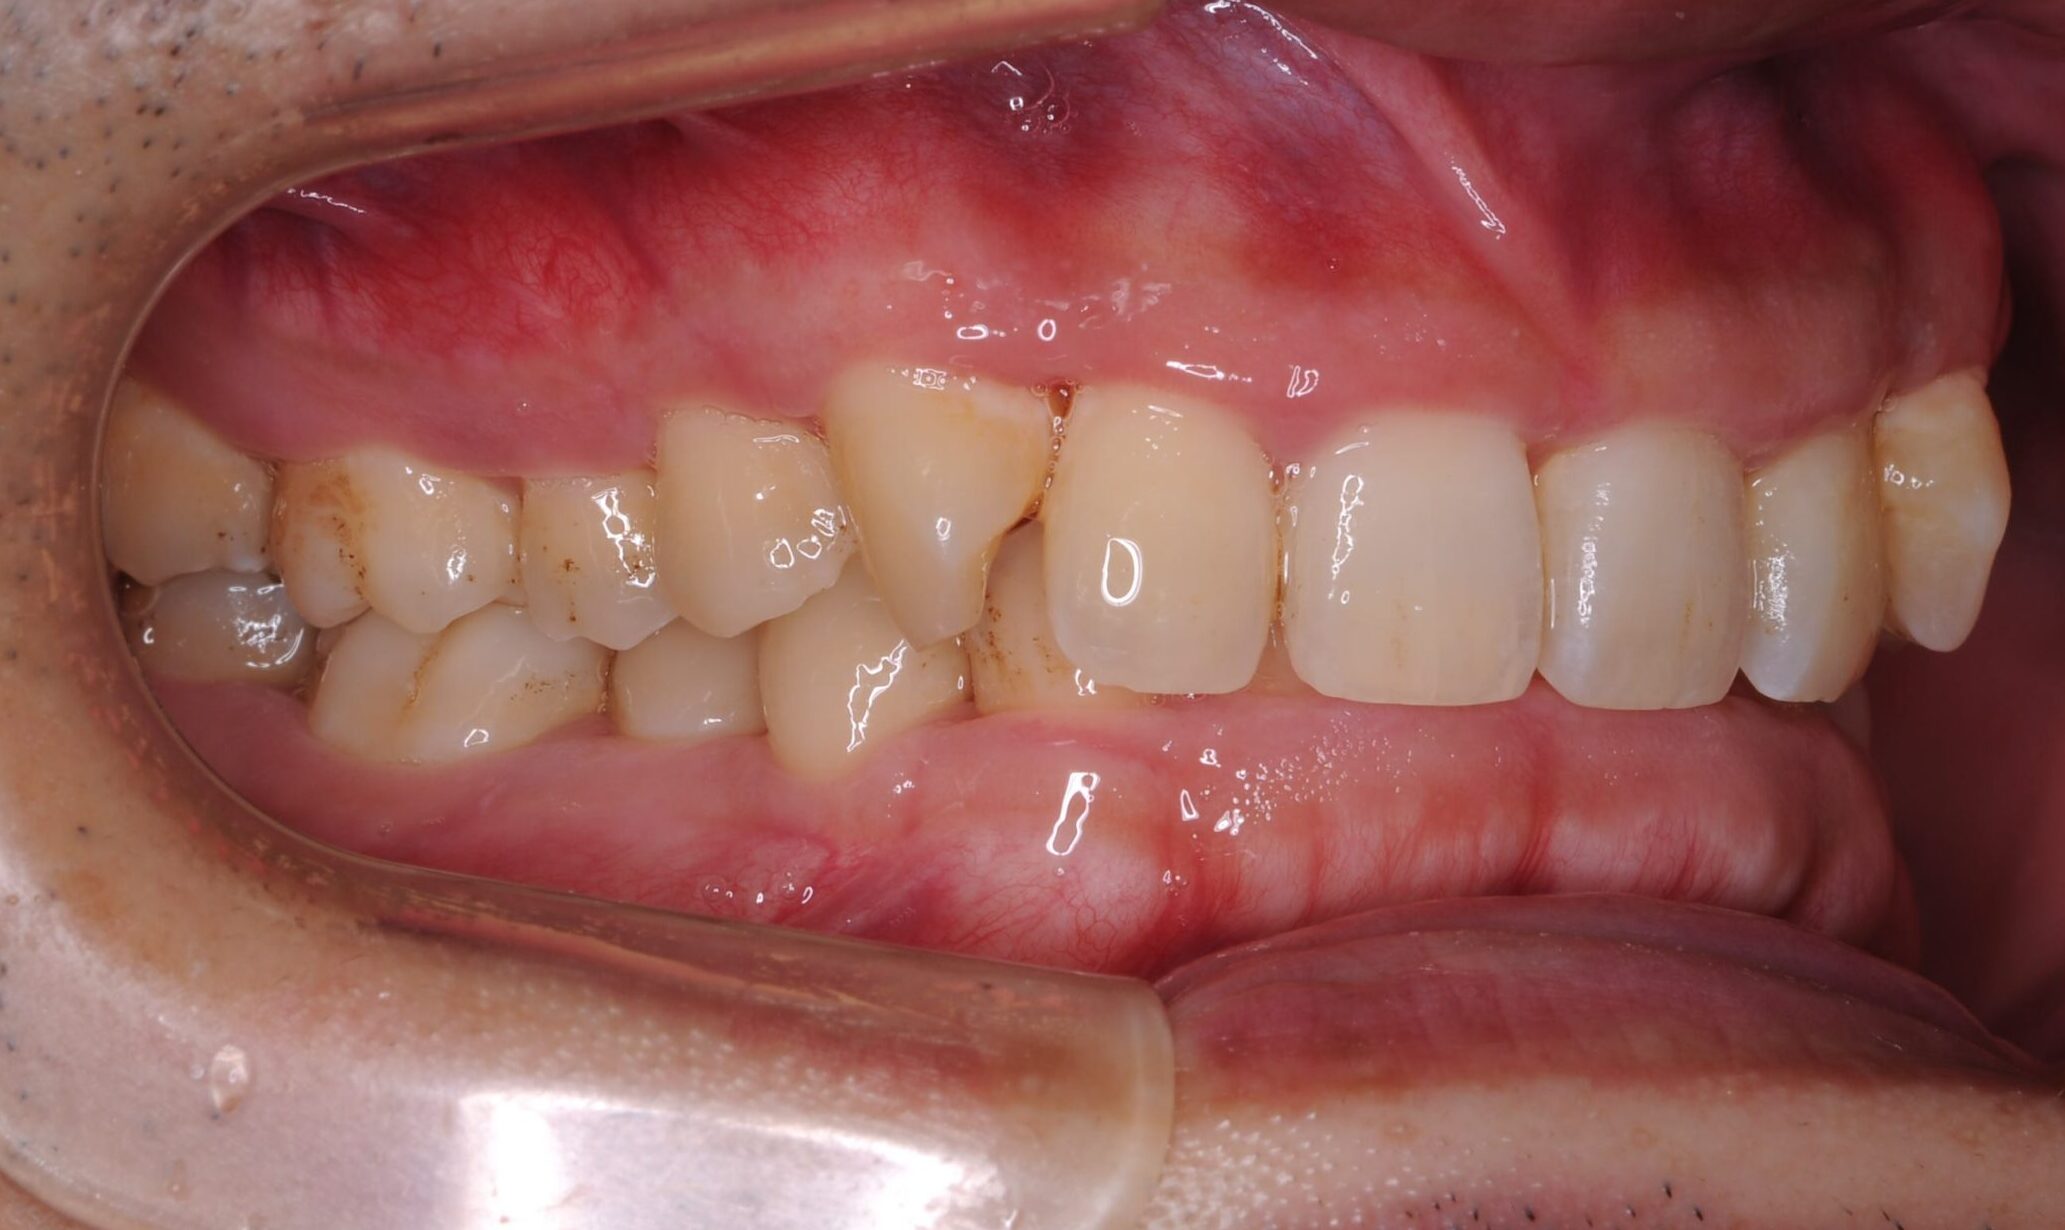

30代・男性

歯茎から出血、歯石除去|中等度に進行した歯周病

症例写真 before

中等度歯周病

歯医者が久しぶりなのでクリーニングをしてほしい、ということで来院されました。

レントゲン撮影、歯周検査などを行なった結果、全体に多くの歯石付着が認められる進行した中等度の歯周病であることが判明しました。ご本人も歯茎から出血することは気になっており、担当歯科衛生士から歯周病について説明を行いました。

今回は歯石の付着が広範囲に渡っており量も多いことから、歯科衛生士による歯周基本治療に加え歯科医師による外科手術も行うことで、徹底的に治療していくことになりました。

歯周基本治療の中ですでに出血量の減少などを実感されており、ブラッシングなどのセルフケアにも積極的に協力していただけたことで外科手術後の経過も順調です。

今後は定期的な歯科検診と毎日のセルフケアで歯周病の進行を抑制し、現在の状態を維持していく予定です。